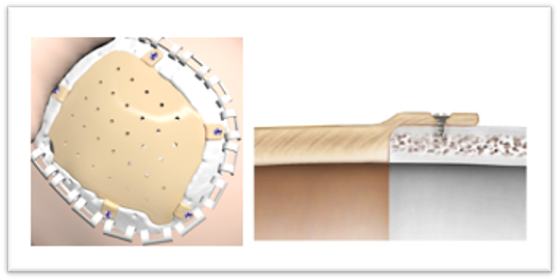

Puente Saliente

Pacientes con mala calidad ósea.